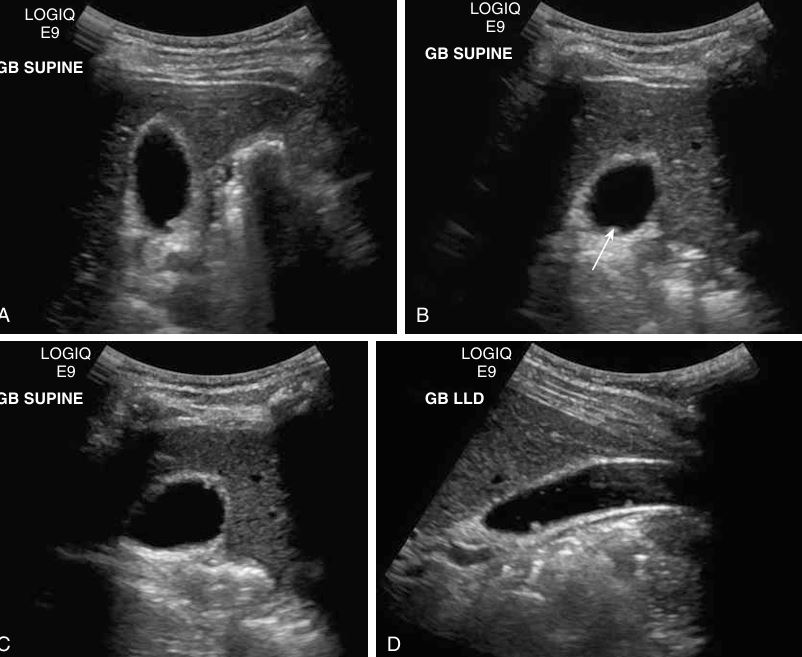

# 1 Pt. c/o RUQ pain, this image looked the same in both supine and LLD positions. Name the pathology

Cholesterolosis showing multiple cholesterol polyps

different patterns of cholelithiasis

what is this showing

Cholelithiasis w Floating Stones

HINT: NO FEVER

Cholelithiasis

Cholelithiasis showing multiple small floating and

nonfloating gallstones